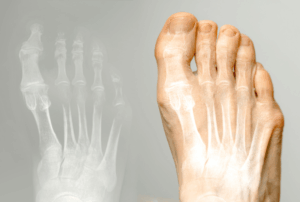

内反小趾(ないはんしょうし)とは、小指の付け根の関節が内側(親指側)に曲がり、

小指全体が外側に反ってしまう状態を指します。

見た目としては、小指が外に傾いて変形し、足の外側に痛みや赤み、

靴との摩擦によるタコや魚の目ができやすくなります。

※図の赤い部分が炎症や圧迫の起こりやすい箇所です。